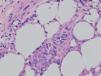

Fig. 4.—Epidermotropismo de células cerebriformes en lesión incipiente de micosis fungoide. (Hematoxilina-eosina, ×200.)

El estudio histopatológico evidencia unos cambios morfológicos distintos según las características clínicas de las lesiones. En las lesiones iniciales los cambios observados pueden no ser diagnósticos y requerir la práctica de numerosas biopsias. En las lesiones más avanzadas se observa un infiltrado en banda formado por células mononucleares de tamaño pequeño o intermedio con núcleo cerebriforme hipercromático sin espongiosis. De forma característica se observa epidermotropismo de los linfocitos cerebriformes atípicos, tanto en forma de células aisladas o formando agregados, los denominados microabscesos de Pautrier (fig. 4). En los estadios tumorales, las biopsias cutáneas muestran un infiltrado monomorfo formado por células atípicas de gran tamaño con frecuentes mitosis que suele afectar a todo el espesor de la dermis. En estas fases tardías no suele observarse epider-motropismo13,14.